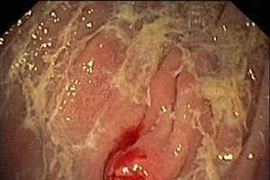

U carcinoid là các thể ung thư bất thường, xuất phát từ nhiều cơ quan trong cơ thể: ruột thừa, dạ dày, ruột non, đại tràng, trực tràng, phổi, buồng trứng và tinh hoàn. …U tiến triển chậm, khó phát hiện, nhiều biến chứng và tiên lượng điều trị dè dặt.